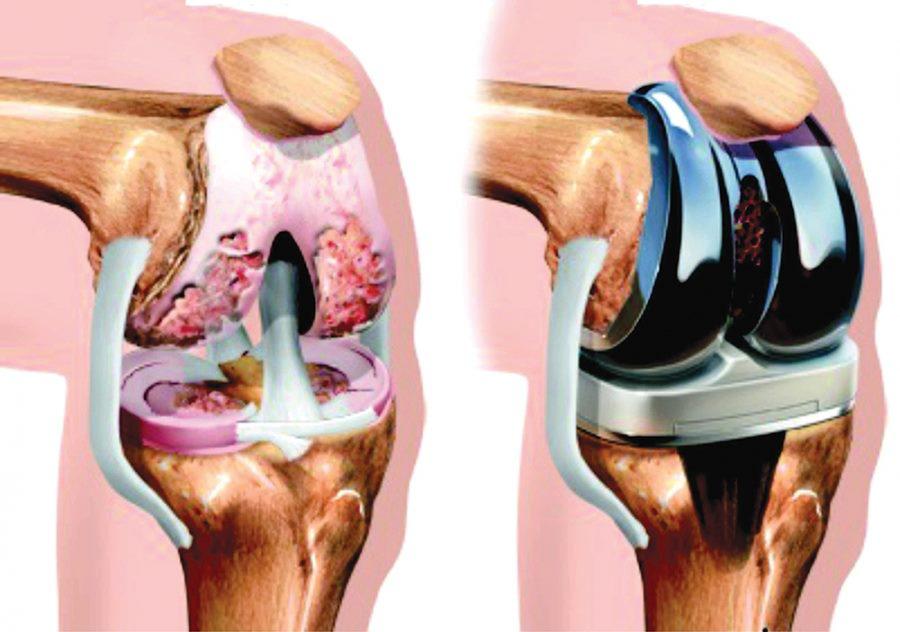

მისი თქმით, ასევე არის მოტეხილობა, როდესაც პაციენტს ოპერაცია ესაჭიროება. ოპერაცია მაშინ კეთდება, თუ მოტეხილი ფრაგმენტები ისეა დამსხვრეული, ერთმანეთს შეცილებული, რომ კუნთების დაჭიმვის გამო მაინც შეცილდება, ამიტომ ასეთ დროს ძვლების გასწორების ბოლო ეტაპი ოპერაციაა და ფრაგმენტების დასაკავშირებლად საფიქსაციო მეტალი გამოიყენება. ის უშუალოდ ძვლის ღრუში თავსდება, ან ძვალზე, ღეროებიც ამის მიხედვითაა და ფირფიტებს სხვადასხვა კონსტრუქცია აქვს.

- არა, ამასთან, არც ოქრო და არც ვერცხლი... ადრე სპეციალურად სამედიცინო მიზნებით მიღებული უჟანგავი ფოლადი გამოიყენებოდა, ის სპეციალური კომპონენტების შენადნობი გახლდათ (რკინა, კობალტი ქრომი გარკვეული პროცენტული შემადგენლობით). უჟანგავი ფოლადი, როგორც ადრე, ახლაც გამოიყენება. მას ბოლო დროს ტიტანიც მიემატა, ანუ მისგან დამზადებული იგივე კონსტრუქციები. ფოლადს ისეთი სამედიცინო პარამეტრები და მახასიათებლები აქვს, რომ ორგანიზმთან კონფლიქტში არ შედის, არ იჟანგება, ტიტანიც ასეთივე თვისების მქონეა, მის შემთხვევაში, დამატებით კიდევ ისაა, რომ ინფექციის მიმართ მეტი ამტანობა ახასიათებს, არის უფრო მსუბუქი, უჟანგავი ფოლადი - მძიმეა. ისე ბოლო დროს მეტად მაინც ტიტანის ნაკეთობებზე გადავდივართ.